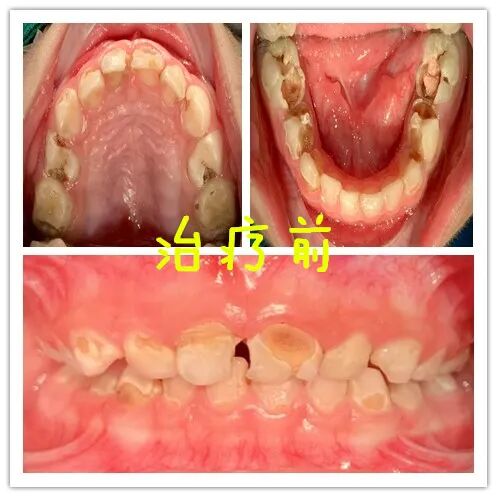

诊室里,刺耳的尖叫声不断回荡。小宇对牙科诊室的环境极度敏感,光是看到牙医工具就开始剧烈抗拒,不断拍打自己的头部。经检查发现,小宇全口20颗乳牙中已有15颗存在严重龋坏,多颗牙齿已经感染到牙髓,但因其严重的触觉敏感和沟通障碍,常规治疗根本无法进行。

手术当天,在麻醉医生的精心监护下,小宇平稳进入睡眠状态。口腔医生团队随后为小宇进行了全面治疗:6颗牙齿进行了根管治疗,6颗深龋牙齿采用了前牙透明树脂预成冠修复。整个过程中,麻醉团队严密监测各项生命体征,确保治疗安全顺利进行。